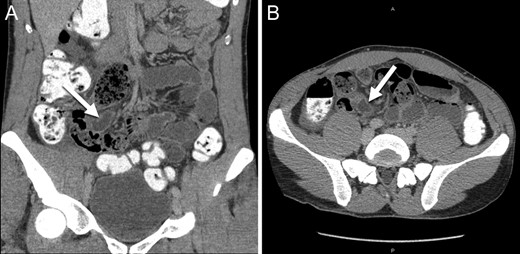

A 27-year-old male presented to the Emergency Department 5 h after the onset of severe right sided abdominal pain. He was afebrile, normotensive with a normal heart rate. He denied any other associated symptoms. His exam was notable for a soft abdomen which was tender to palpation in the right lower quadrant with associated voluntary and involuntary guarding. He had a Rovsings and obturator sign. His white blood cell count was 13 with 79% polys. A CT scan of the pelvis with rectal contrast was obtained. The diagnostic interpretation was acute appendicitis with likely perforation. The appendix was reported to be dilated, measuring 9 mm in diameter with associated wall thickening, surrounding fat stranding and hyperemia. Fluid was noted in Morrison’s pouch, along the paracolic gutter and in the pelvis (Fig. 1). The decision was made to proceed to the operating room for a laparoscopic appendectomy.

Abdominal CT scan ((A) coronal and (B) axial slices) showing a dilated and inflamed tubular structure indicated by the white arrows misinterpreted as acute appendicitis.